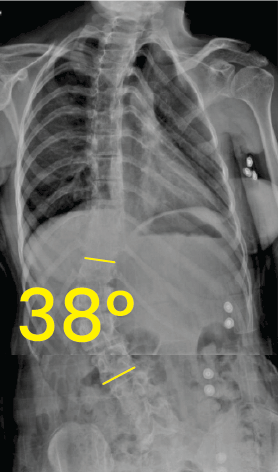

Göğüs ve bel omurgasını gösteren röntgen görüntüsü, omurga eğrilik açısı 50 derece olarak işaretlenmiş.Torakal omurga röntgeninde 38 derece skolyoz açısı ve omurgada metal vida yerleşimi.

Göğüs röntgeninde omurgada 38 derece skolyoz açısını gösteren sarı çizgiler ve 38° rakamı.Göğüs ve lomber omurgada 29 derece skolyoz eğrisi gösteren röntgen görüntüsü.